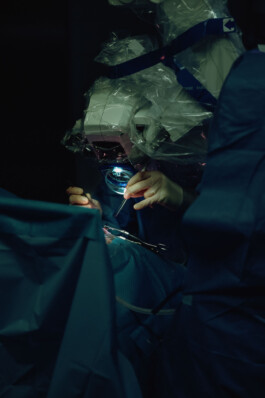

Veronika Wolter setzt Cochlea-Implantate ein. Und sie trägt selbst welche. Ohne die wäre sie taub. Sie ist die einzige gehörlose HNO-Chefärztin der Welt.

Text: Lucia De Paulis

VERONIKA WOLTER

editorial for Chrismon